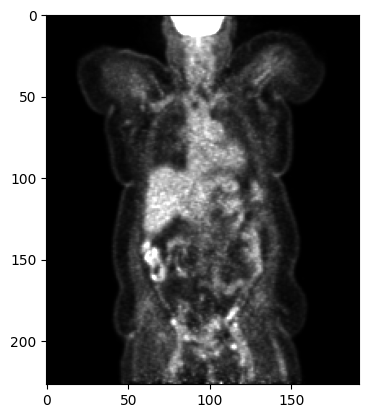

[5]:

pet_image = pet.clone()[0]

array = np.array(pet_image)

print(pet_image.shape)

# select one slice for plotting

plt.imshow(array[::-1, 95, :, :], cmap='gray', vmin=0, vmax=15000)

plt.show()

(227, 192, 192, 1)

../../_images/tutorials_imfusion-sdk_1_working_with_images_10_1.png